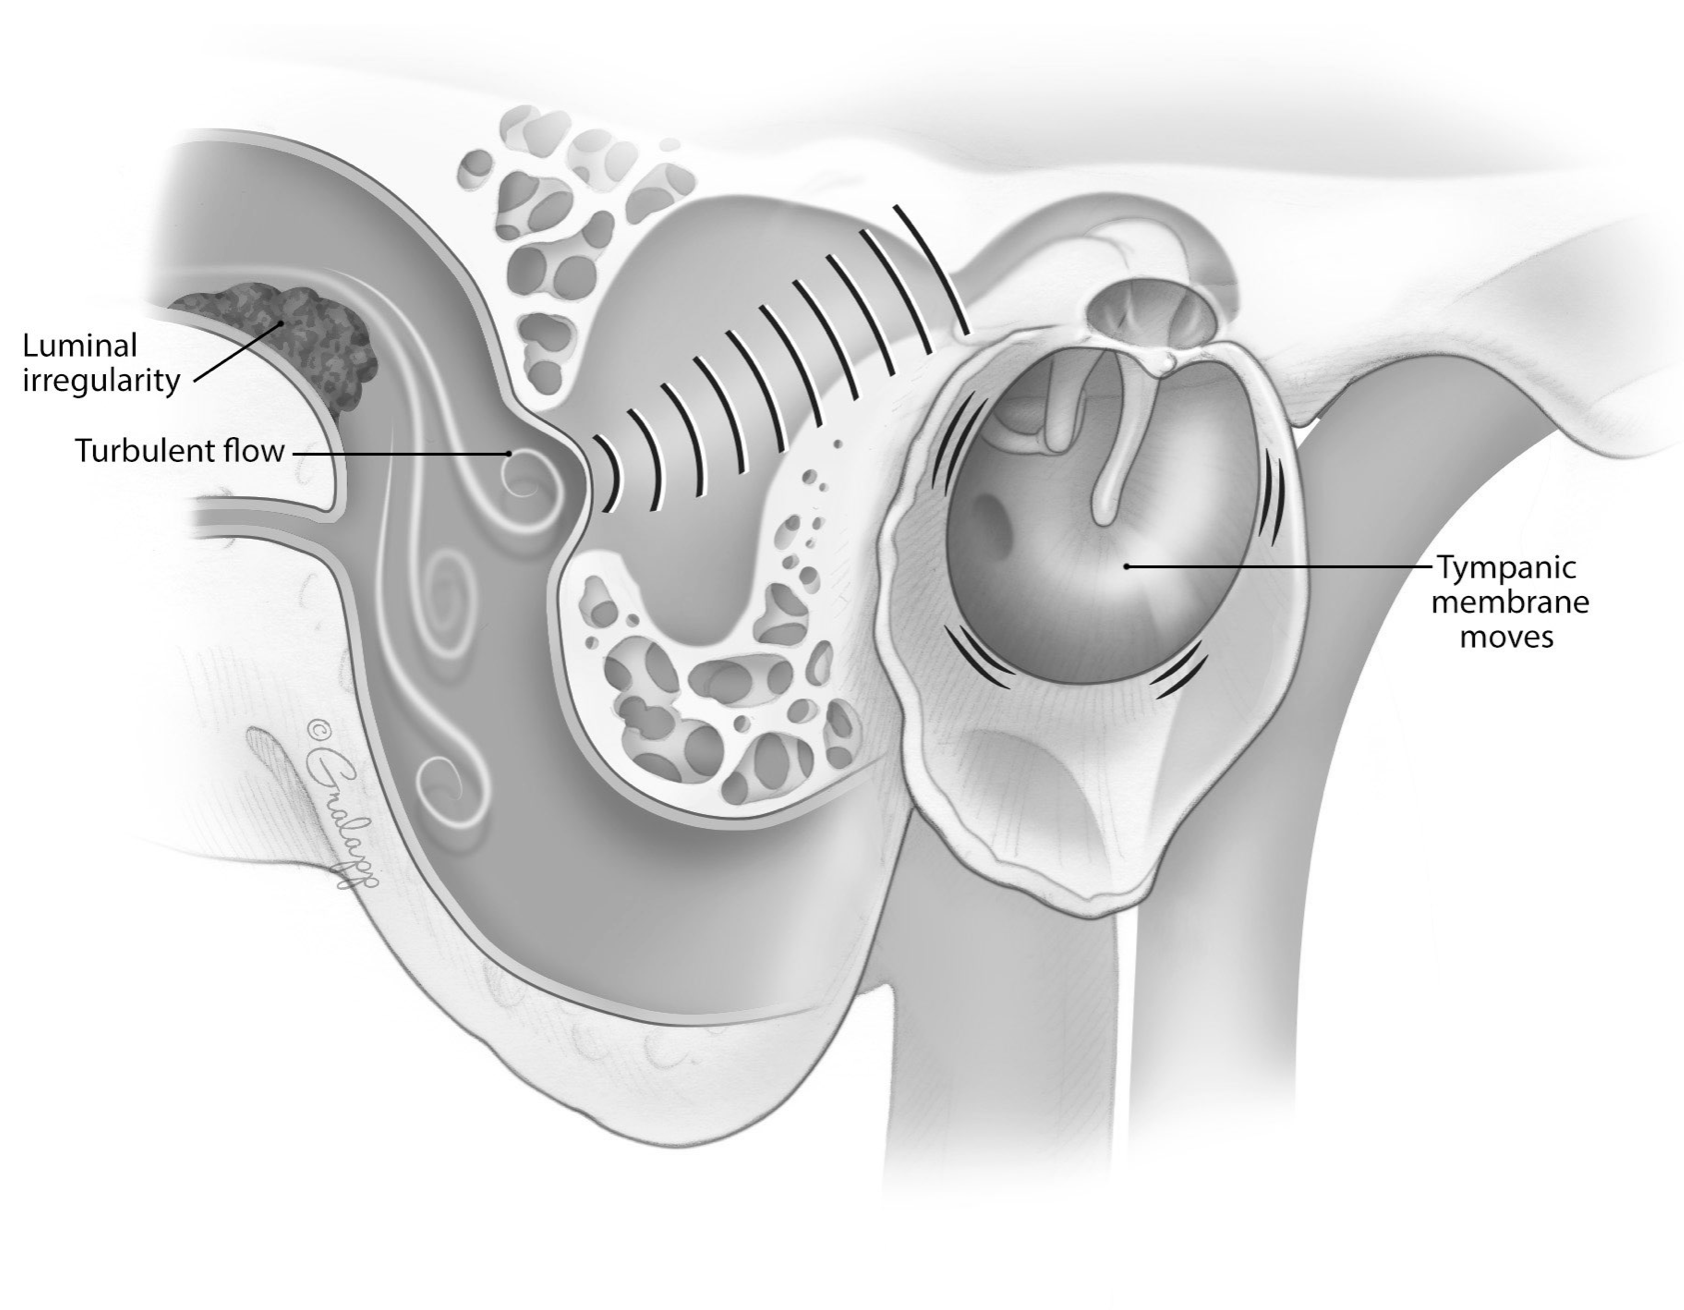

Advanced otology encompasses complex ear and skull base conditions requiring specialized surgical care. We offer cochlear implants and bone conduction implants for hearing loss, treat acoustic neuroma and temporal bone tumors, and perform stapes surgery for otosclerosis. Our team also manages cholesteatoma, superior canal dehiscence, and other advanced ear conditions. Select a topic below to learn more.